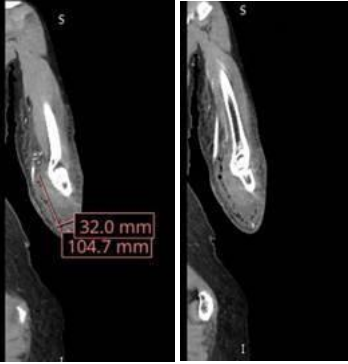

A 72-year-old Caucasian female with Alzheimer’s dementia, hypertension, hyperlipidemia, and hypothyroidism developed progressive swelling and erythema of the left forearm after being bitten by her adult son. She was initially treated at an outside hospital with empiric antibiotics, but worsened, prompting transfer. On arrival, she was hemodynamically stable. Laboratory findings revealed leukocytosis (white blood cell count of 13.2 cells/mcL), hypophosphatemia (1.5 mg/dL), and elevated C-reactive protein (34.19 mg/dL). Computed tomography demonstrated extensive subcutaneous gas and fluid extending from the distal humerus to the wrist (3.2 × 10.5 cm), concerning for NSTI (Fig. 1).

Figure 1: Coronal (a) and axial (b) Computed tomography images of the left forearm demonstrating an extensive subcutaneous fluid collection measuring 3.2 × 10.5 cm and a gas pattern consistent with necrotizing soft-tissue infection. Images progress from proximal to distal.